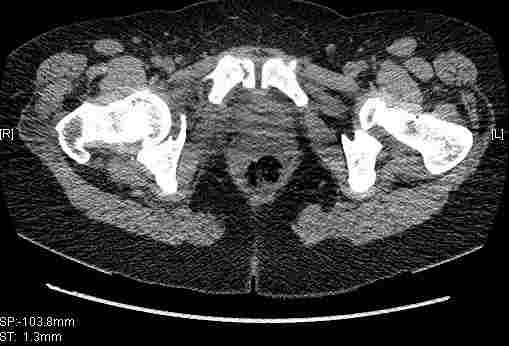

Остальные срезы.